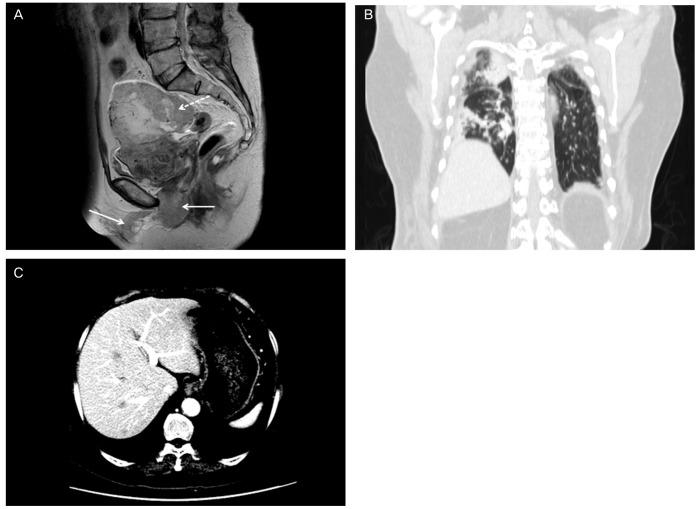

Primary vaginal cancer represents only 1% to 2% of malignant neoplasm of the female genital tract. Here, we report a 68-year-old woman who showed a vaginal tumor extending to urethra and clitoris, a 10 cm-sized mass in left adnexa and multiple metastases in lung and liver. Vaginal biopsy showed squamous cell carcinoma of vagina and she was diagnosed as International Federation of Gynecology and Obstetrics stage IVB vaginal cancer. Palliative surgery including left salpingectomy, tumorectomy, and clitoris mass excision was performed. Concurrent chemoradiation therapy (CCRT) with six cycles of 5-fluorouracil and cisplatin was administered. The patient had a complete remission of 20 months after treatment. At a 40-month follow-up, there was no evidence of local recurrence or distant metastasis. We can suggest that CCRT is very effective in treating primary squamous cell carcinoma of the vagina, not only in locally advanced but also systemically involved vaginal cancer in selected cases.

原发性阴道癌仅占女性生殖道恶性肿瘤的1%至2%。在此,我们报告一名68岁女性,其阴道肿瘤延伸至尿道和阴蒂,左侧附件有一个10厘米大小的肿块,肺部和肝脏有多处转移。阴道活检显示为阴道鳞状细胞癌,她被诊断为国际妇产科联盟IVB期阴道癌。进行了姑息性手术,包括左侧输卵管切除术、肿瘤切除术和阴蒂肿块切除术。给予了六个周期的5-氟尿嘧啶和顺铂同步放化疗(CCRT)。患者治疗后完全缓解20个月。在40个月的随访中,没有局部复发或远处转移的证据。我们可以认为,CCRT在治疗原发性阴道鳞状细胞癌方面非常有效,不仅对局部晚期阴道癌有效,而且对某些系统受累的阴道癌也有效。